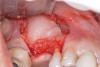

Fig. 18  Subgingival calculus and severe bone loss.

Figure 18

The patient had been referred for an implant consultation for the mandibular right canine. She had very deep probing depths on the lingual. When the flap was raised, a significant amount of subgingival calculus was seen as a local risk factor (Figure 18). However, she had no significant pathology to remove from the situation. Debridement was performed the same as in Case 3 with the rotary ultrasonic and manual instrumentation.

The defect was obturated with mineralized freeze-dried bone and hydrated with platelet-derived growth factor. As with any growth factor, when implementing it clinically, all growth factors require a carrier to bring that growth factor to the desired site, which do not elicit an inflammatory response. In this situation, it is the mineralized freeze-dried bone allograft. This combination was demonstrated by Rosen et al8 to be efficacious in treating intrabony defects. A biologic approach was taken both in terms of the graft and membrane (Figure 19). Primary closure was achieved.